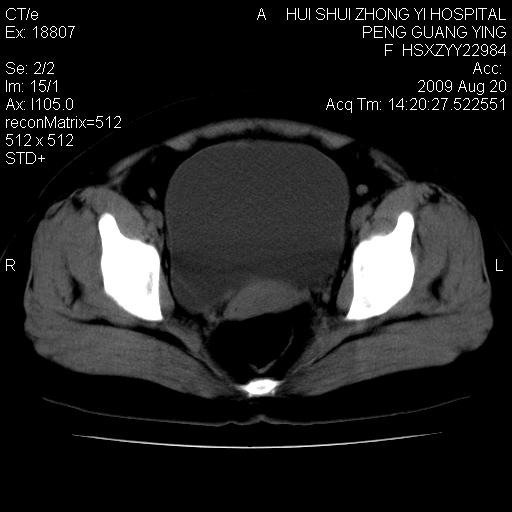

标题: CT21707:女,42岁,因发现下腹部包块2月。 [打印本页]

标题: CT21707:女,42岁,因发现下腹部包块2月。

目前的影像表现显示肿块位于腹腔及盆腔,但具体定位,分清来源较困难,是否来源于卵巢、子宫无法定论,子宫直肠及子宫膀胱周围脂肪间隙尚较清晰,如果患者有过腹腔好或者盆腔手术史,也可以形成不典型的血中,最好手术后定为定性,我期待结果。

软组织密度,与子宫一致。双侧卵巢形态、密度好,不支持来源于卵巢。